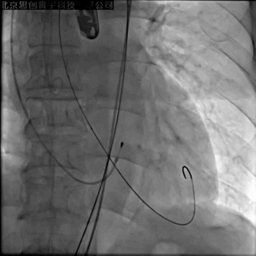

第一次释放,瓣膜位置偏高

应用PLUS回收支架,重新定位

释放后造影见中度瓣周漏,彩超提示支架没有充分打开